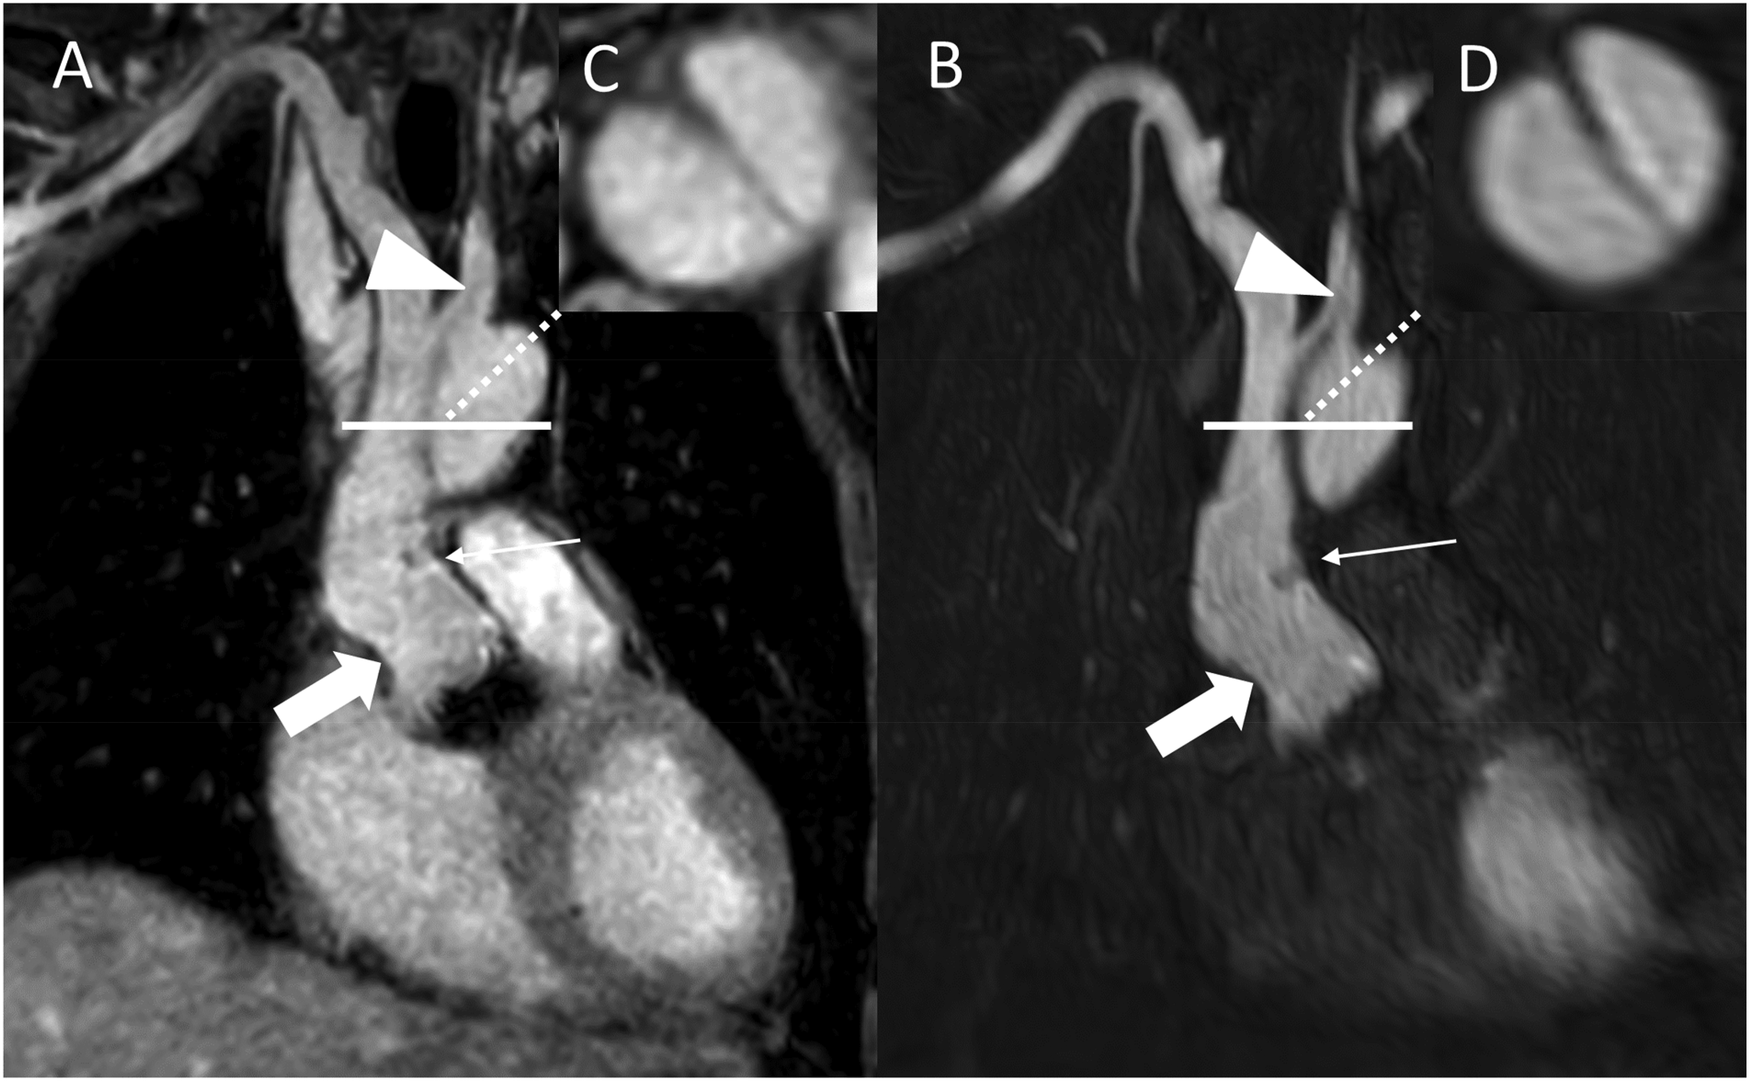

Figure 4

REACT [(A), source images, water-only, coronal plane] and CE-MRA [(B), source images, coronal plane] in a 54-year-old male after bentall procedure due to Stanford type A aortic dissection (AD). The delineation of the aortic graft (wide arrow: mid graft, thin arrow: distal anastomosis) and remaining AD affecting the aortic arch and the left common carotid artery (arrowhead) is comparable in both sequences. The axial reformation [square; REACT: (C) CE-MRA: (D)] serves to highlight the delineation of the dissection membrane in both sequences. CE-MRA, contrast-enhanced magnetic resonance angiography; REACT, relaxation-enhanced angiography without contrast and triggering.